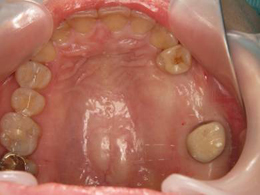

左上の奥歯の骨が少なくてそのままではインプラントを入れられなかったため、オペと同時にサイナスリフトをしました。

今ではしっかり噛めています。骨が極度までない場合でもほとんどがインプラントオペと同時にサイナスリフトが可能です。